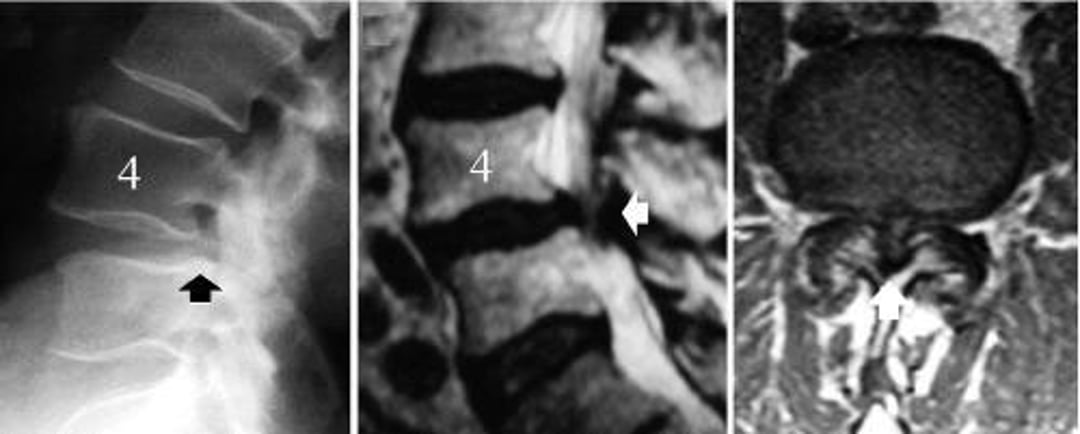

左の画像はL4のすべりを示す腰椎のX線側面像である(黒矢印,L5椎体の後縁とL4の後縁がずれている)。中央の画像は神経構造物の圧迫(白矢印)を示すMRI正中矢状断像である。右の画像は,脊椎変性すべり症のL4-5のレベルにみられる重度の脊柱管狭窄症を示したMRI水平断像である。